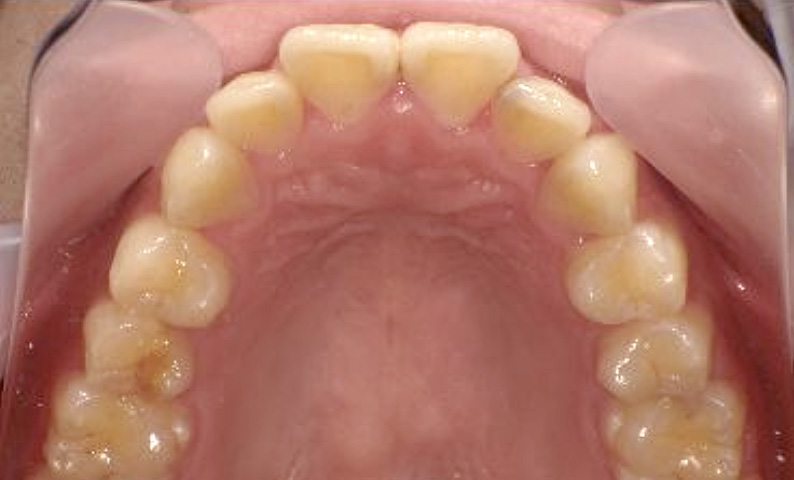

症例_023 上顎だけの部分矯正

治療期間:9ヶ月金額:30万円+税女性前歯のガタガタ上の前歯だけ

| Before | After |

|---|---|

|